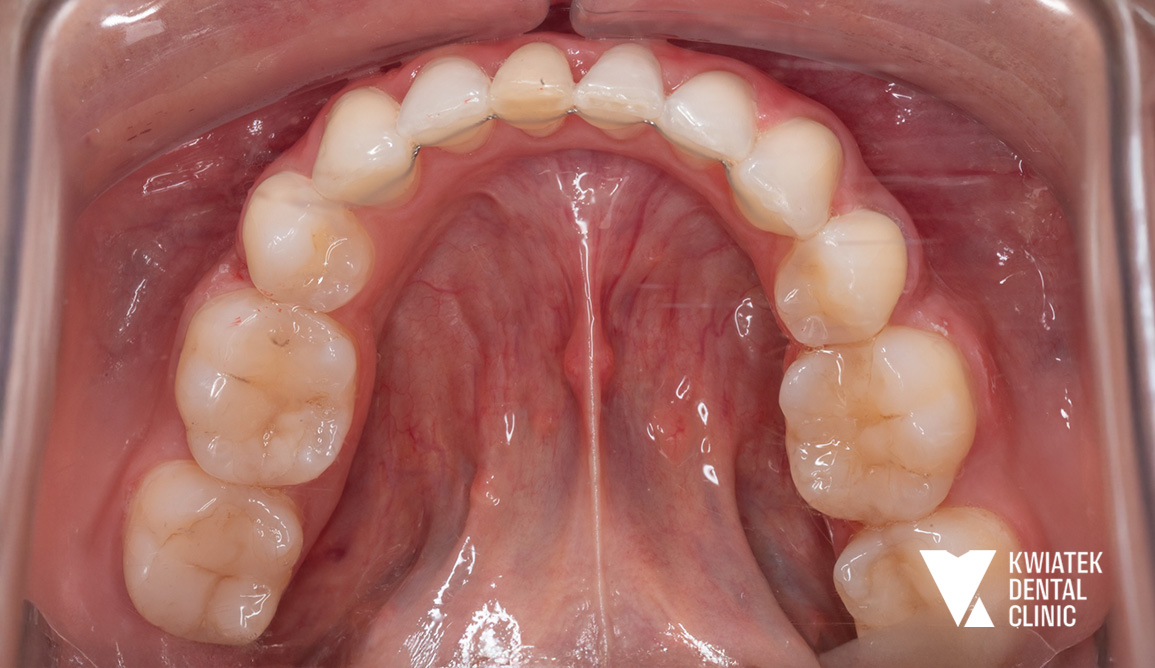

PO

Etap retencji

Po zakończeniu leczenia aktywnego zastosowano retainery stałe oraz ruchome, aby utrwalić uzyskany efekt i zapewnić jego długoterminową stabilność.

Efekt końcowy to pełna metamorfoza uśmiechu zarówno pod względem zdrowotnym, jak i estetycznym.

Uzyskano:

• prawidłowe ustawienie zębów w łukach

• zamknięcie przestrzeni po ekstrakcjach

• poprawę relacji zgryzowych

• naturalny, harmonijny uśmiech